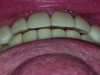

Pretreatment occlusal view of maxillary arch.

Figure 8

Functional: Attrition was noted on the teeth that were not protected with full-coverage crowns (Figure 8 and Figure 9). While wearing a Kois deprogrammer for about 1 month prior to restorative treatment, the mandibular teeth wore a notch in the deprogrammer platform, confirming clenching and the possibility of an impaired cortical control of the central pattern generator (Figure 10).1 All platform variables were verified and proper design of the Kois deprogrammer was followed. (The notch in the deprogrammer was repaired, leaving a smooth, flat surface to allow the proper position of the mandible to be determined.) The temporomandibular joint examination revealed normal opening with no joint sounds. The load and immobilization tests were normal. All the muscles, except the masseter, had no tenderness to palpation. Trigger points were palpable within the masseter muscles, which were hypertrophied. The diagnosis was determined to be occlusal dysfunction with the addition of awake bruxism and clenching. Upon questioning, the patient shared that he clenched while playing tennis daily, which he was very passionate about. The evidence that he was not grinding at night was the fact that tooth No. 11 was extremely cupped and not flattened. This ruled out a diagnosis of sleep bruxism, as the incisal edge would have become flat due to lateral movements of the mandible.